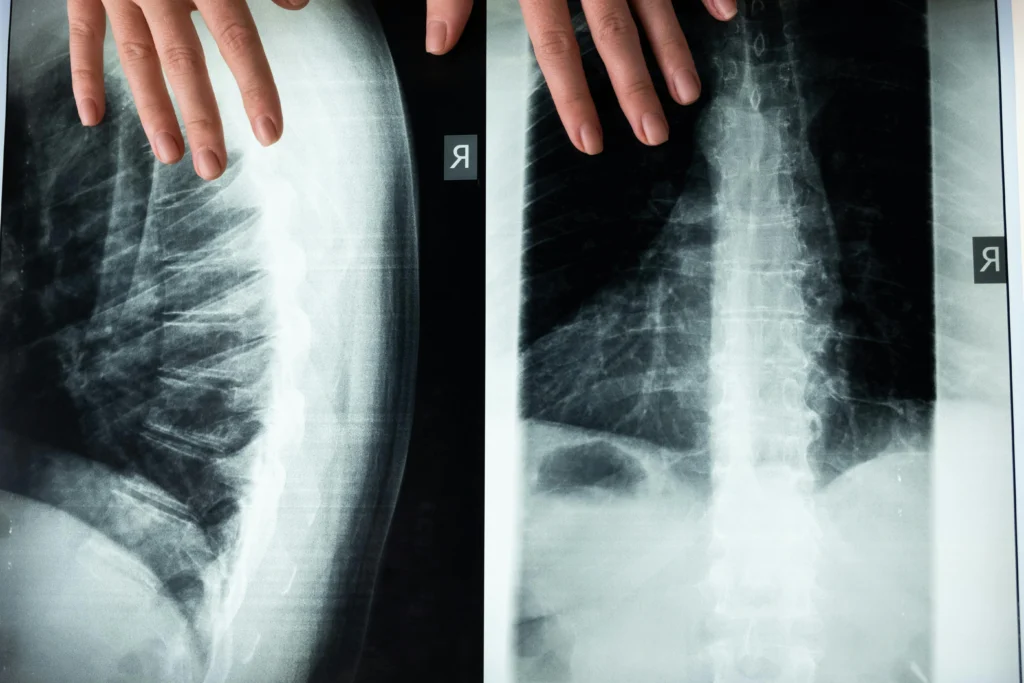

Kyphoplasty vs Vertebroplasty Explained

Kyphoplasty and vertebroplasty are minimally invasive spinal procedures used to treat painful vertebral compression fractures, most commonly caused by osteoporosis. Both involve stabilizing a fractured spinal bone using medical cement, but kyphoplasty also includes a step to create space inside the vertebra before cement injection. This key difference can affect pain relief, spinal alignment, and […]